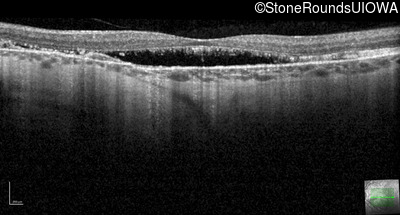

Optical Coherence Tomography - Right - 20/20 -3 sc

Exemplar / OCT Stack